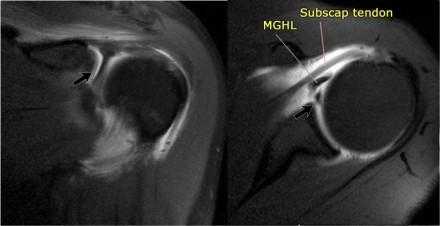

Комплекс Буфорда

Комплекс Буфорда это врожденный вариант строения суставной губы в виде отсутствия ее передневерхних отделов в области на 1-3 часа и утолщение средней плече-лопаточной связки.

Определяется в 1,5 % случаев.

На аксиальных изображениях слева может быть виден комплекс Буфорда.

Отсутствуют переднеие отделы суставной губы в области на 1-3 часв, утолщена средняя плече-лопаточная связка.

Утолщенная средняя плече-лопаточная связка не должна обшибочно приниматься за смещенную суставную губу.

Всегда по возможности необходимо прослеживать ход средней плече-лопаточная связки сверху вниз от фиброзно-хрящевой губы гленоида к плечевой кости.